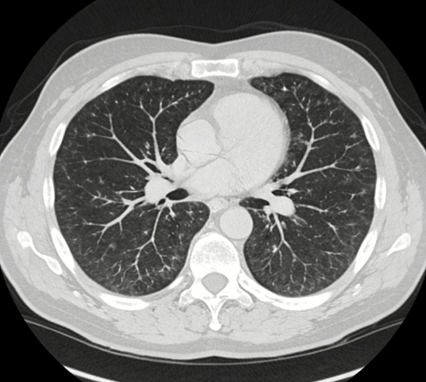

核心原理:“切面包”式扫描

LDCT本质仍是CT。它通过旋转的X射线球管对人体进行快速、连续的螺旋式扫描,受检者深吸气屏气4-6秒即可完成全肺扫描,借助迭代重建技术,能生成肺部毫米级精度的横断面图像,如同将肺部切成一片片薄面包来观察,无重叠、分辨率高,微小病灶清晰可见。